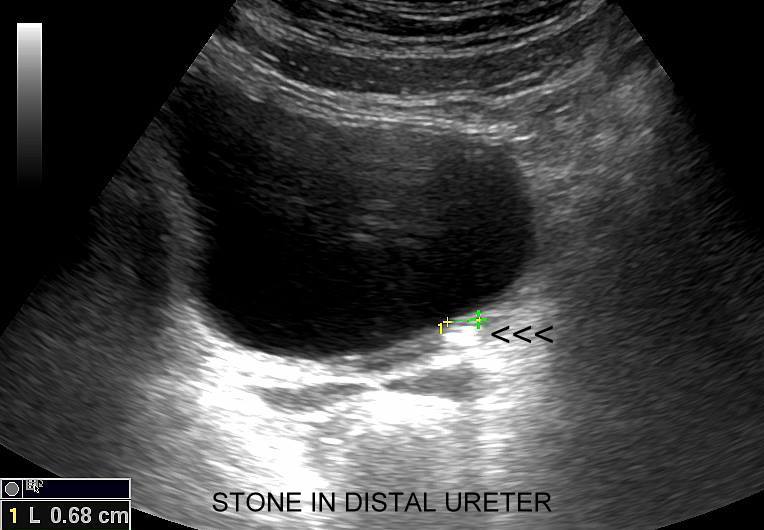

Badania obrazowe służące wykrywaniu kamicy moczowej to badanie RTG, CT, lecz przede wszystkim badanie USG. W badaniu USG nerek w prezentacji B kamica nerkowa widoczna jest w sytuacji, gdy złogi są odpowiednio uwapnione, odpowiednio duże oraz nie zlewają się z zatoką tłuszczową miedniczki nerki. Zasadniczo złogi w trybie B będą widoczne wyraźniej, gdy położone są w miąższu nerki; z kolei w miedniczce nerkowej, gdy są na tyle duże, że dają artefakt cienia. Czasem w celu uwidocznienia złogu przydatne jest wyłączenie wspomagania typu x-beam.

Objawy kolki nerkowej wynikają z mechanicznego drażnienia i wtórnego ranienia ścian moczowodu w trakcie przemieszczania się kamienia, a ich lokalizacja zależy od miejsca, w którym aktualnie złóg się znajduje. Najczęściej może on utknąć w naturalnych zagięciach i przewężeniach moczowodu, tj. na złączu miedniczkowo-moczowodowym, na skrzyżowaniu moczowodu z naczyniami biodrowymi oraz przy pęcherzu moczowym. W omawianych warunkach dominują zasadniczo bóle o charakterze ostrym. Druga przyczyna objawów związanych z kolką nerkową wynika z zastoju moczu oraz podwyższonego ciśnienia w układzie kielichowo-miedniczkowym; w tym wypadku dominują bóle tępe.